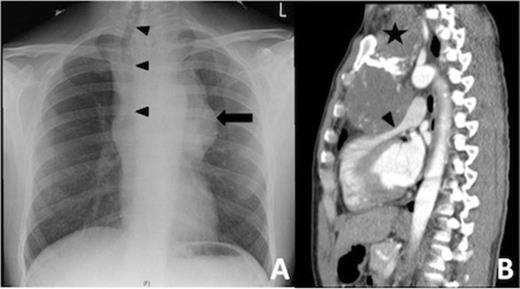

A 26 year old male presented with sudden onset of severe shortness of breath and headache, more intense on the right side while swimming. This was associated with tunnel vision in his left eye, facial flushing and numbness on the left side of his face and down his left arm. On clinical examination he was found to have a murmur and investigation with a chest X-ray (CXR) (Fig 1A) revealed a large mediastinal mass which was causing significant displacement of the trachea to the right. A subsequent computed tomography (CT) (Fig 1B) scan demonstrated a large superior mediastinal mass, which was extending down into the anterior mediastinum and compressing the right ventricular outflow tract (RVOT) of the heart. A Doppler study with transthoracic echocardiogram showed the RVOT to have a systolic gradient of 60 mmHg and was the most probable source of the murmur. After discussion at the multidisciplinary meeting it was decided to proceed with surgery.

Patient CXR (Figure 1A) with a large shadow (black arrow) of the mass in the superior mediastinum. Due to its size the trachea was displaced far to the right (black arrow head). Sagital views of the CT scan (Figure 1B) showed the mass (black star) in the superior mediastium extending inferiorly into the anterior mediastinum causing obstruction of the right ventricular outflow (black arrow head). The aortic arch was also pushed posteriorly.